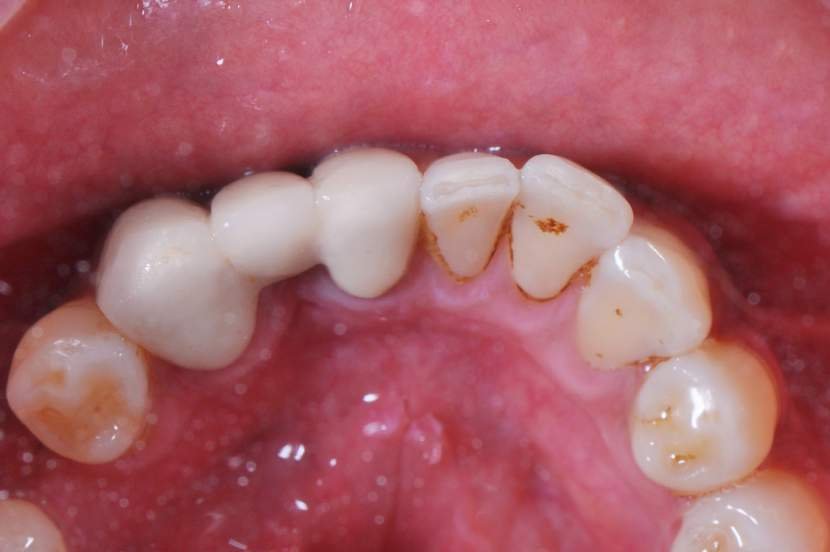

O implante Slim Pilar de corpo único com os diâmetros de 2,5 e 3,0 milímetros (Fig. 2) foram desenvolvidos para superar o desafio de pequenos espaços desdentados.

Os implantes Slim Pilar, apresentam alta versatilidade protética possibilitando aplicação de coroas Cimentadas ou Parafusadas (Fig. 3). O Sistema protético é simplificado, utilizando o mesmo sistema aplicado em implantes Implacil Cone Morse para transferentes, coifas e análogos. E a aplicação é tanto para elementos Unitários como para Múltiplos.